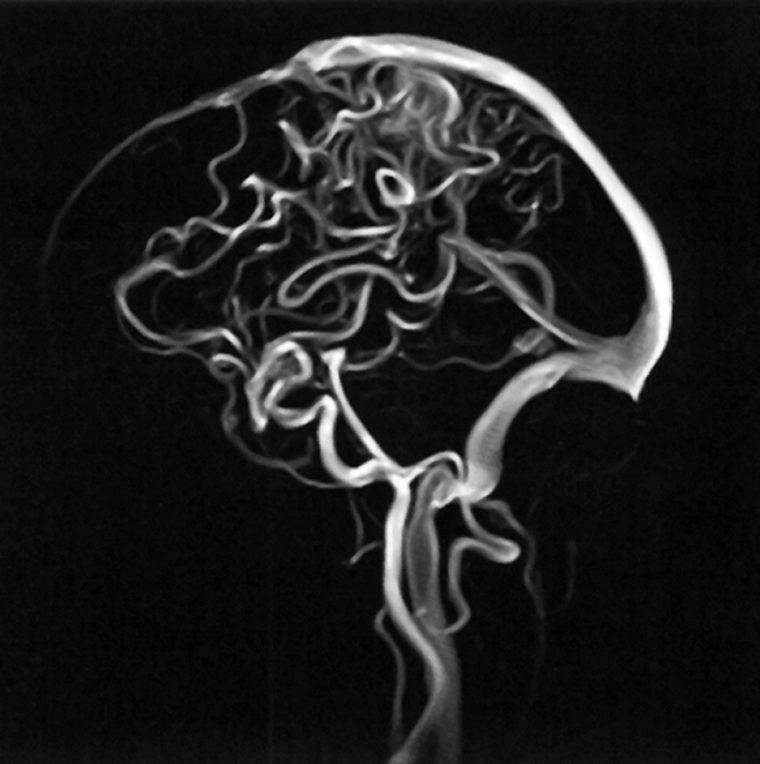

Figura 14-12:

Time-of-flight angiography.